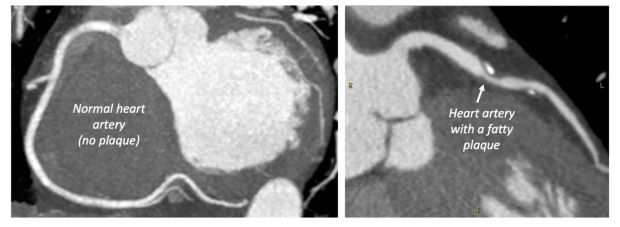

A CT coronary angiogram is used to directly visualise the heart arteries and the fatty deposits (plaques) that can develop within them. This fatty plaques can mean your heart is not getting the blood supply it needs, which can cause chest pain (angina) and heart attacks.

The CT coronary angiogram is the first line test recommended by UK guidelines for assessing patients presenting chest pain to outpatient cardiology or chest pain clinics. It will tell your cardiologist whether you have fatty plaques in your coronary arteries, the more plaques you have the more likely a heart attack is in the future.

It will also tell them whether these plaques are likely to be obstructing blood flow to the heart muscle and causing your chest pain.